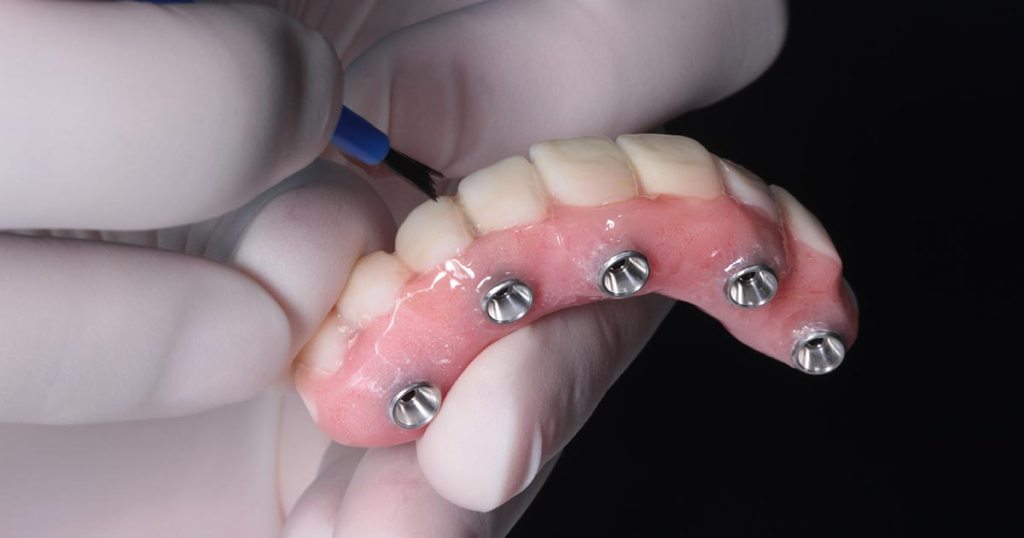

O Protocolo All-on-4 é uma técnica de reabilitação oral fixa que utiliza quatro implantes dentários estrategicamente posicionados para suportar uma prótese total fixa em pacientes totalmente edêntulos ou com indicação de exodontia total.

Dois implantes são instalados na região anterior, geralmente de forma axial, enquanto os dois implantes posteriores são posicionados com inclinação distal, normalmente entre 30° e 45°.

Após o período de osseointegração, geralmente entre três e seis meses, a prótese definitiva é confeccionada.

Nessa fase, são considerados aspectos estéticos, fonéticos, oclusais e biomecânicos, com escolha criteriosa dos materiais e desenho protético adequado.